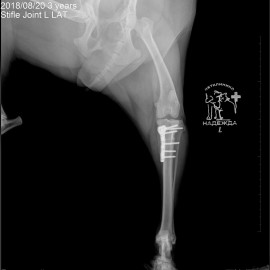

Наш пациент собака по кличке Артемон. Обратились с жалобами на остро развившуюся хромоту на заднюю левую лапу. После осмотра и рентгенологического исследования был поставлен диагноз - разрыв передней крестообразной связки левого коленного сустава. Была проведена операция- TPLO.

Снимки 3-4 после проведённой операции.